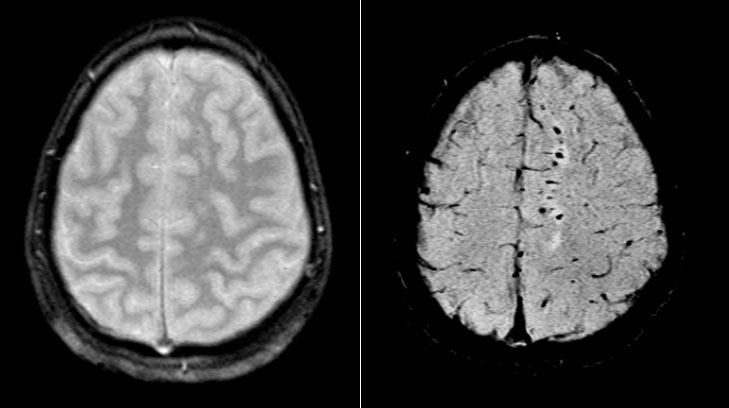

Медицинские аспекты и диагностика субдуральной гигромы мозга